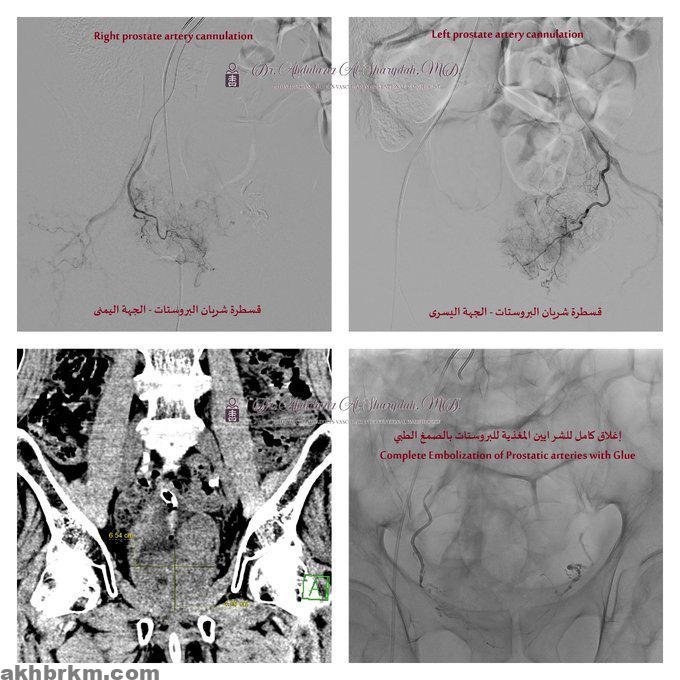

و كشفت الفحوصات الأولية بما في ذلك الأشعة المقطعية للبطن والحوض، وجود تضخم كبير في البروستاتا يضغط على جدار المثانة تم رصده من خلال منظار المثانة تحت إشراف استشاري المسالك البولية د.عبدالله الزهراني والذي تبين وجود تجلطات دموية ونزيف نشط من غدة البروستاتا، مما استدعى تدخلاً طبيًا عاجلًا بالتعاون مع قسم الأشعة – وحدة الأشعة التداخلية والقسطرة.

و تم إجراء قسطرة لإغلاق الشرايين المغذية للبروستاتا عبر شريان الفخذ باستخدام تقنية الاصمام بالصمغ الطبي تحت التخدير الموضعي، دون الحاجة إلى أي شق جراحي، و هذه التقنية المتقدمة مكنت الفريق الطبي بقيادة استشاري القسطرة والأشعة التداخلية للكبار والأطفال د. عبدالعزيز الشريدة من تحقيق نتائج فعالة وسريعة، حيث شهد المريض تحسنًا كبيرًا في اليوم التالي، وتمكن من التبول بشكل طبيعي دون أي نزيف، مما سمح بخروجه من المستشفى بعد يوم واحد بحالة صحية مستقرة.